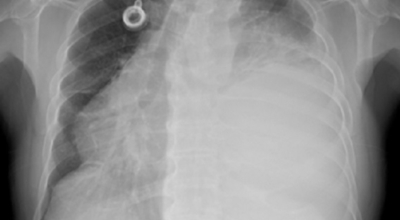

폐암 검사는 X-ray를 통해서 검사하는데 , 크기가 작거나 구석에 위치한 경우 확인이 어려운 경우도 있습니다. 그리고 조직 검사를 통해서 정확한 진단을 하게 되어요. 폐암이 발견되면 종양의 크기나 전이 여부 , 위치에 따라서 수술 여부를 결정하게 돼요.